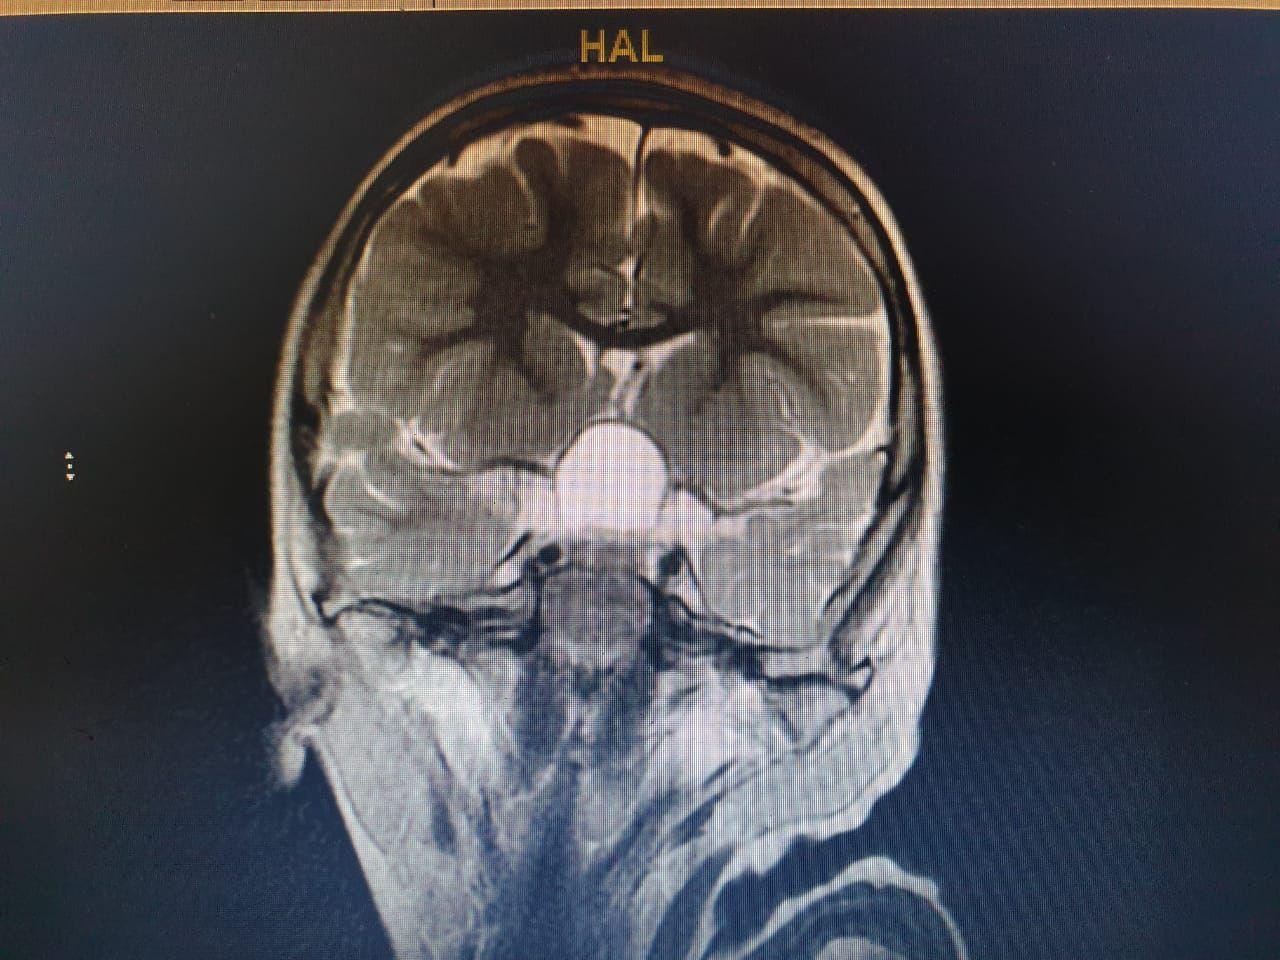

وعلى الفور أجرى الفريق فحوصات متقدمة  ، واتضح وجود"ورم" بقاع الجمجمة ، ومتصل بالغدة النخامية.

وأشار المتحدث الرسمي بصحة الطائف سراج الحميدان ,أن  الفريق الجراحي للمخ والأعصاب ، تدخل جراحيا بعملية استمرت 7 ساعات لإزالة الورم بالرغم من خطورة الوضع ، وتكللت بالنجاح بفضل الله .